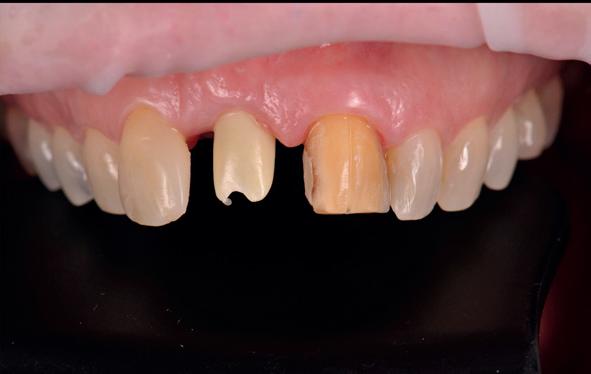

Er werd meer bekend over de gedragingen van het bot rond de “microgap” en daarmee kwam er meer begrip over hoe een implantaat goed te plaatsen in de esthetische zone. In het midden van de jaren negentig kwam daar de kennis bij hoe, op een verantwoorde manier en met behulp van guided-bone-regeneration, een implantaat in de esthetische zone te plaatsen (afbeelding 6-10).

Van vooral functionaliteit verschoof de indicatie naar esthetiek. De zachteweefselchirurgie en vaak voorbehandeling van zachte weefsels voor implantologie kreeg veel meer aandacht (afbeelding 11-14).